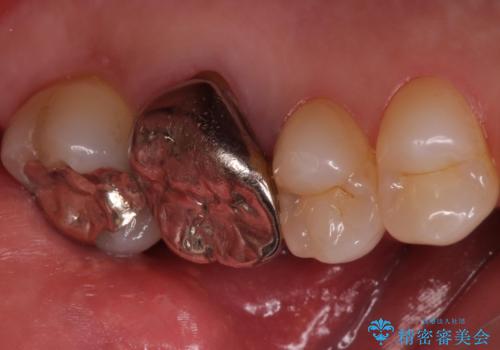

- 左上の奥歯を何とか保存していた患者様です。

今回、残していた歯根から歯茎が大きく腫れ、長期的な予後を期待できないことを考慮し、抜歯してブリッジでの治療を行いました。